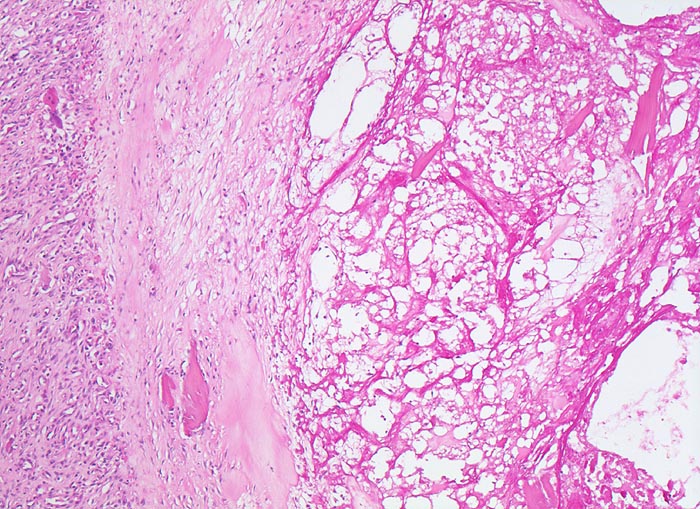

• Sekundäre Sklerose der freiliegenden Spongiosa mit Anbau von breiten Faser- und Lamellenknochensäumen an die alten Bälkchen.

• Herde von metaplastischem Faserknorpel in der Gelenkfläche.

• Nekrosebezirk in der Spongiosa (Geröllzyste) umgeben von einem Granulationsgewebssaum und Narbengewebe.